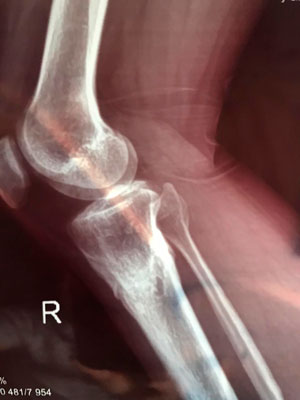

Дата операции - 15.06.2019г.

Дата снятия аппаратов - 25.09.2019г.

Срок сращения - 100 дней.